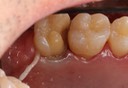

Kyle Chock #30 pre-op

Kyle Chock #30 amalgam removal

Kyle Chock #30 prep